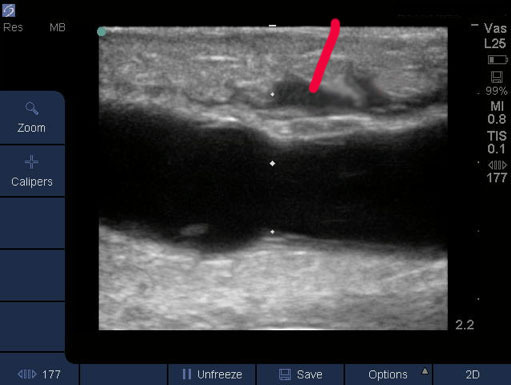

Dialysis Vessel Edema Image